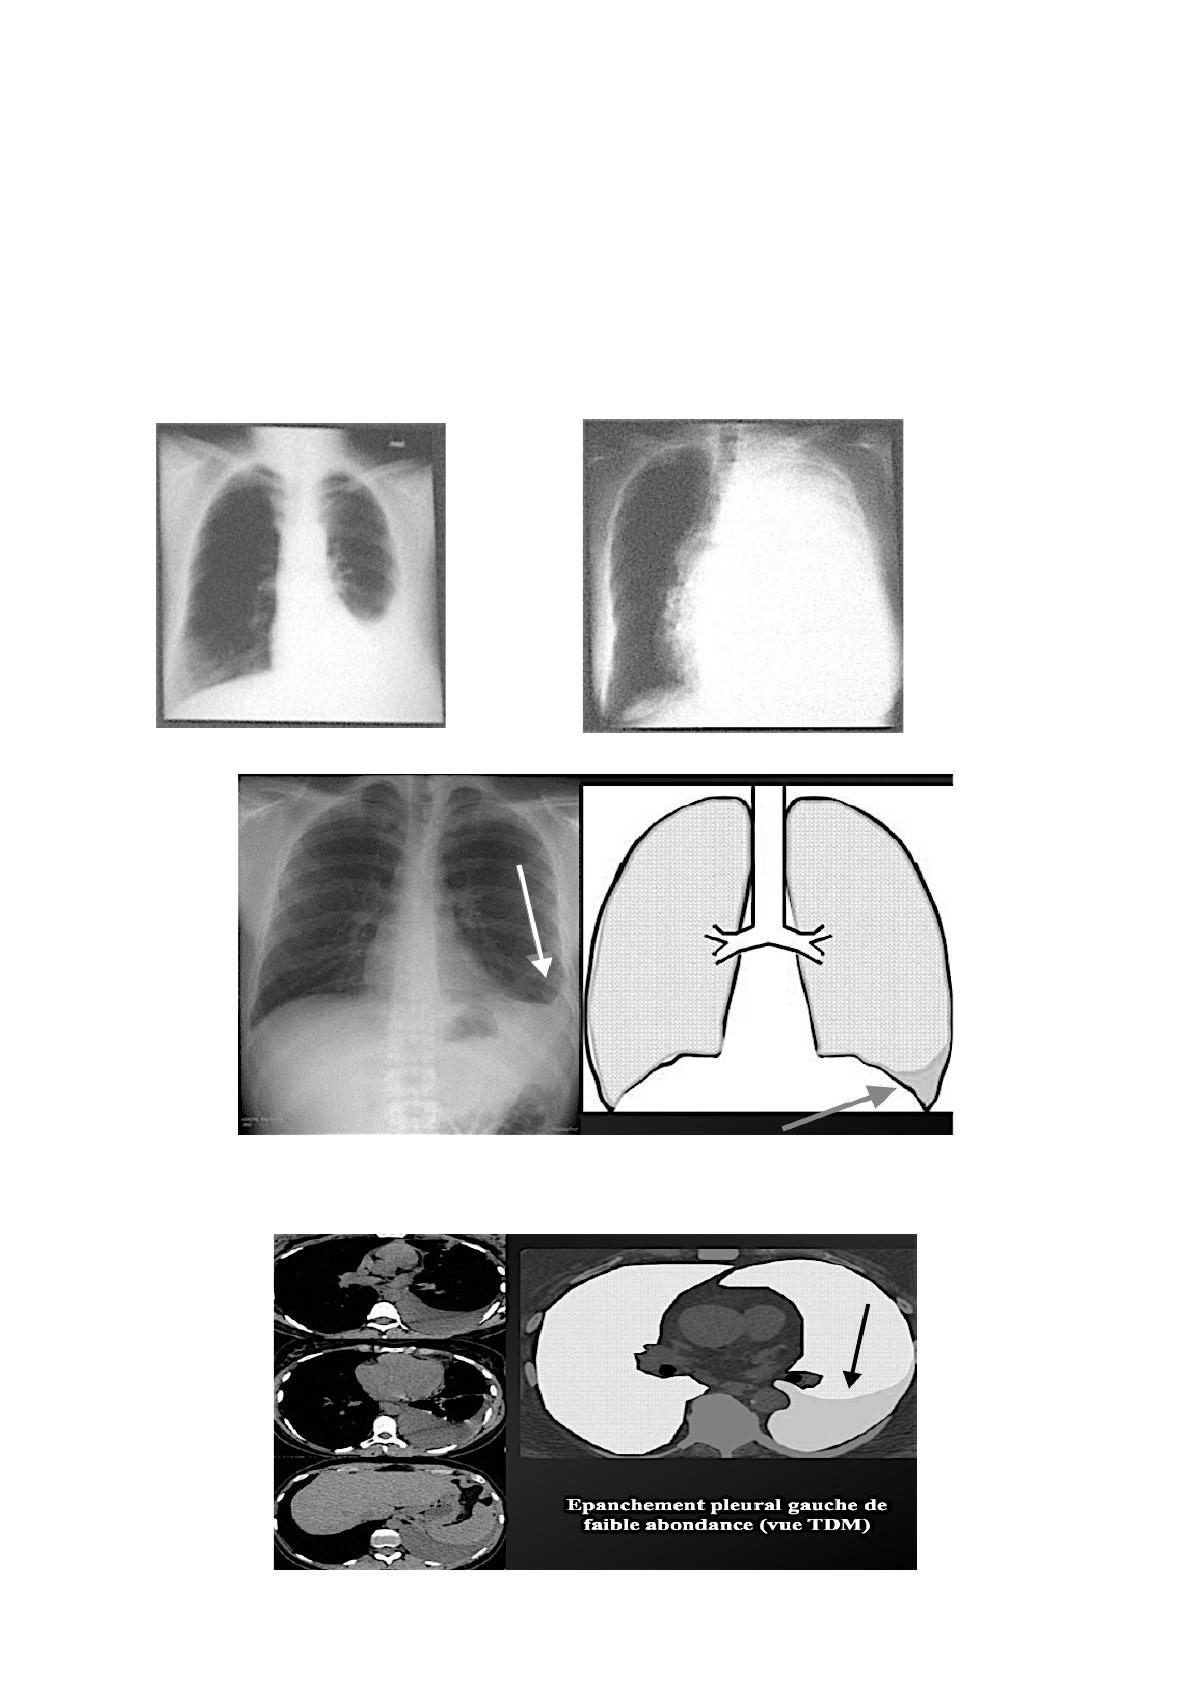

APPAREIL RESPIRATOIRE – Pleurésie et pneumothorax

–anomalie sur une radiographie du thorax/,*+-)+2+J(+/((*

M+(K--1(L